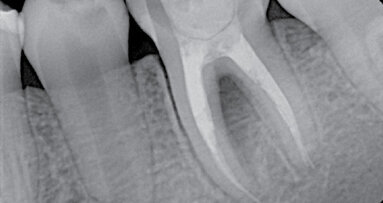

Během stomatologických výkonů vytvářejí rotační a jiné nástroje částice zvané aerosoly (obr. 5). Ty mohou obsahovat zbytky dentinu a skloviny, dentinové smear layer nebo úlomky kompozitu, provizorního cementu nebo past. Do vzduchu se uvolňují také bioaerosoly obsahující sliny, krev a další biologické tekutiny. Vysoká míra kontaminace bioaerosoly se vyskytuje na brýlích a maskách stomatologů a jejich asistentů.